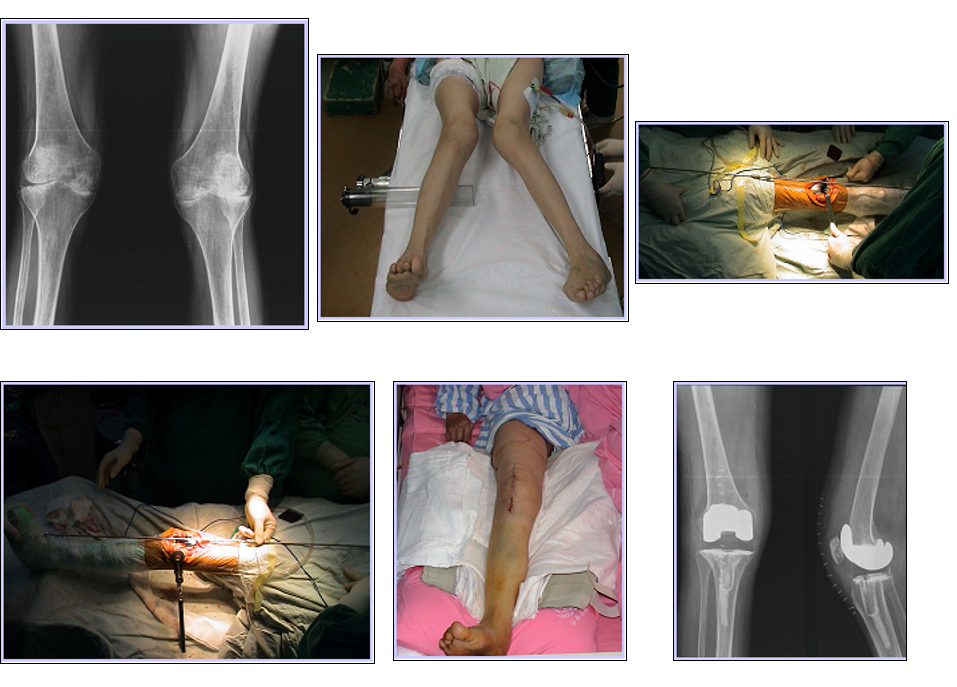

关键三、矫正膝关节外畸形

先做伸直位平衡

松解内侧关节囊 MCL

截骨

切除内侧骨赘,内后角骨赘

平衡内外侧间隙